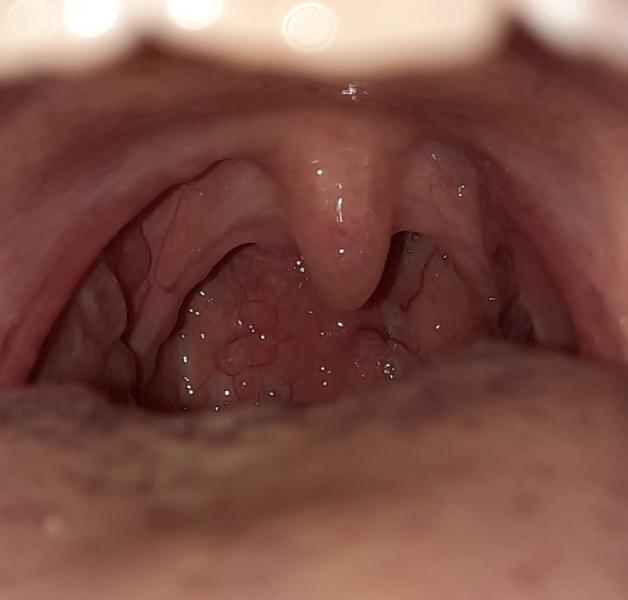

Что за шишка в горле у ребенка? Завтра к врачу

Добрый вечер мамочки может быть кто-то сталкивались с такой ситуации, у сына появилась в горле такое, завтра к врачу поедем

Похоже на фарингит (но я не врач)